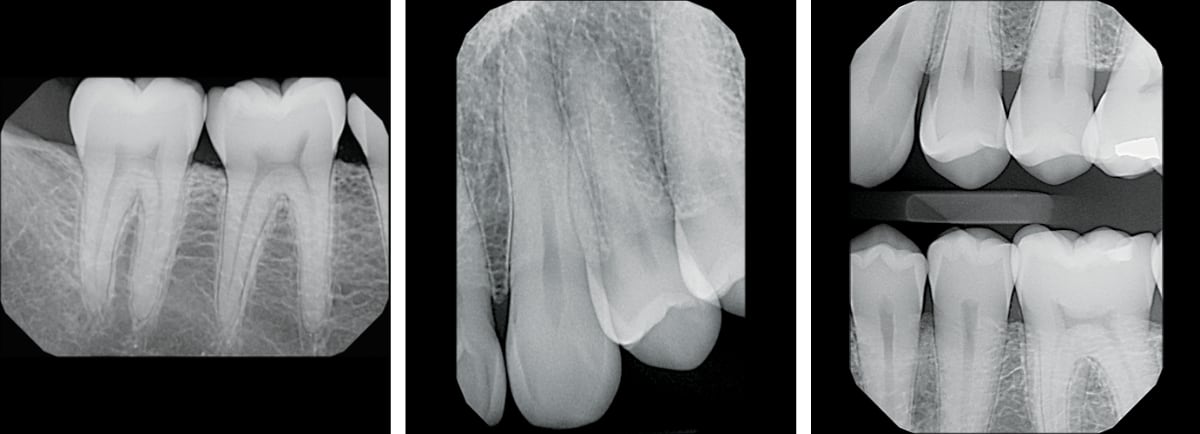

Рентгеновские снимки зубов

Использование рентгеновского и другого высокоточного оборудования при диагностике позволяет в режиме реального времени получить точные изображения нужных участков полости рта в оптимальном разрешении.

• Радиовизиограф (визиограф, видеограф, дентальный снимочный аппарат) — прибор, преобразующий лучевые рентгеновские данные в цифровое изображение на компьютере в режиме реального времени. Стоматолог с помощью визиографа контролирует процедуру лечения не отходя от кресла с пациентом. Прибор позволяет оперативно сделать снимок и получить изображение проблемного зуба.

• Цифровой 3D ортопантомограф — позволяет сделать панорамный снимок нужной области черепа или отдельного зуба. Прибор незаменим при протезировании, лечении, имплантации, исправлении прикуса (ортодонтии) и т. д.